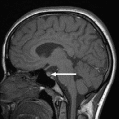

Магнитно-резонансная томография. Наиболее информативный метод исследования гипофиза. При магнитно-резонансной томографии визуализируются передняя и задняя доли, воронка гипофиза, возможно оценить симметричность гипофиза, положение воронки, состояние спинки турецкого седла. На МР-сканах структура аденогипофиза гомогенная, изоинтенсивна с белым веществом мозга.

Аденомы гипофиза на Т1 ВИ – визуализируются как зоны со сниженным по сравнению с остальной тканью аденогипофиза сигналом, на Т2ВИ – как зоны с повышенным сигналом. При внутривенном контрастировании аденомы накапливают контрастное вещество и можно более детально оценить структуру опухоли.

Рисунок Магнитно-резонансная томограмма головного мозга в сагиттальной плоскости. Микроаденома.